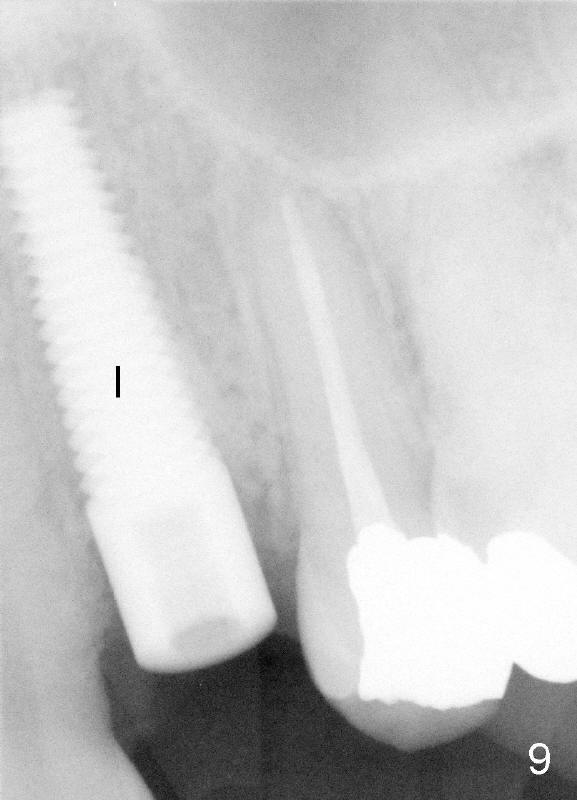

After tooth extraction, the osteotomy is initiated in the palatal socket (compare Fig.6,7 (CBCT, not the same case) with a pilot drill (pink outline). The osteotomy is enlarged by a series of reamers until the apical diameter (3.5 mm, Fig.8) of the prospective tapered implant (5x20 mm, Fig.9 I). The socket is obliterated by the tapered implant (Fig.9) with simultaneously achieving primary stability. This looks less over engineering than the first case.